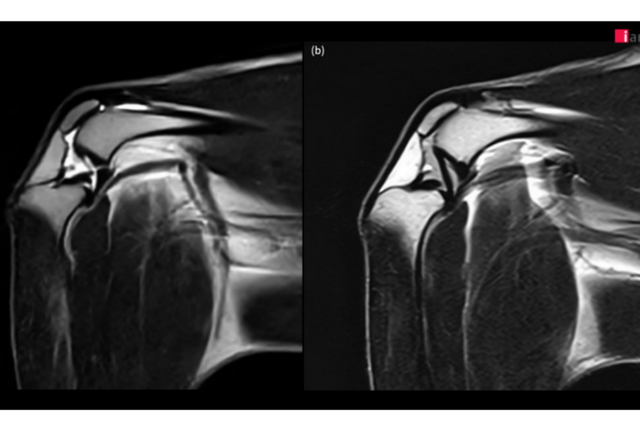

4kg 정상견의 전십자인대(a), 후십자인대(b). (사진=이안동물의학센터)

이안동물의학센터가 국내 동물병원 중 최초로 도입한 AI 기반 MRI 소프트웨어를 통해 무릎(Stifle joint) MRI 촬영 화질을 획기적으로 향상시키며 반려동물 정형외과 진단의 새로운 기준을 제시하고 있다고 밝혔다. 특히 이안동물의학센터는 이 소프트웨어로 복잡한 무릎 관절 내 구조물에 대한 세밀한 관찰이 가능해지면서 정확한 진단과 치료 전략 수립에 있어 큰 진전을 이루고 있다.

2023년 말부터 본격 가동된 이안동물의학센터의 AI 기반 MRI 소프트웨어는 딥러닝 알고리즘을 활용해 노이즈를 효과적으로 제거하고, 이미지 선명도를 대폭 향상시켰다. 특히 무릎 관절처럼 작은 구조물들이 복잡하게 얽혀 있는 부위에서 기존 영상 기법으로는 명확하게 파악하기 어려웠던 인대, 연골, 활액낭 및 인접한 근육 등의 세부 구조물까지 뚜렷하게 확인할 수 있어 정밀 진단에 큰 도움이 되고 있다.

이안동물의학센터는 정형외과에서 무릎 질환은 MRI로 진단하기에 가장 까다로운 분야 중 하나라며, AI 기술을 통해 MRI의 화질이 개선됨에 따라 십자 인대 파열, 연골 손상, 활액막 질환, 힘줄 질환 등 다양한 무릎 질환을 보다 빠르고 정확하게 진단할 수 있게 됐다고 설명했다.